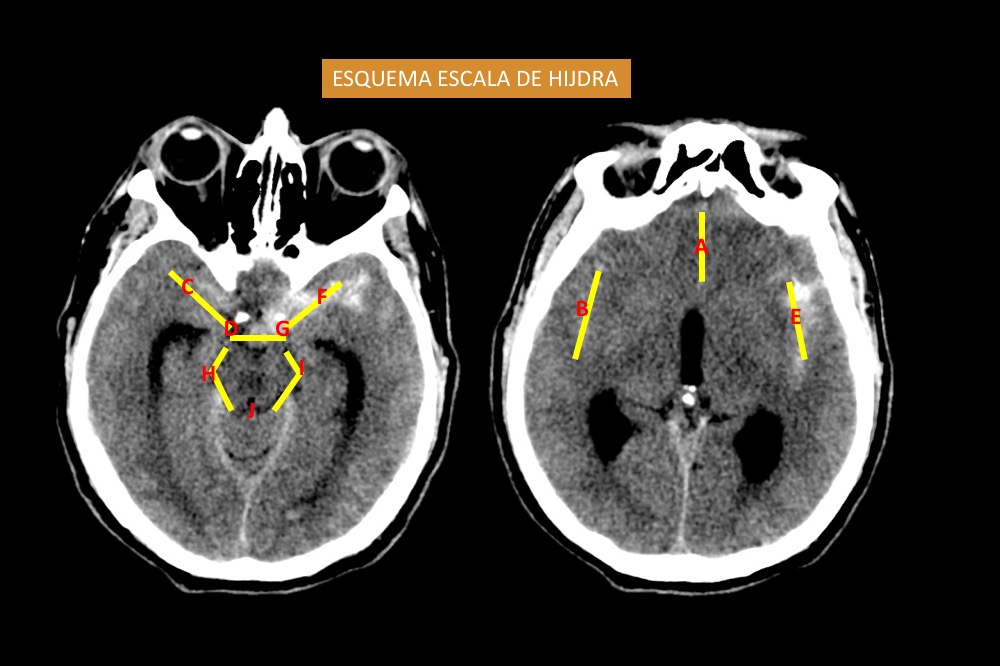

Inicialmente se dividió el patrón de la HSA en supratentorial e infratentorial y el hemisferio que ocupa la HSA. La cantidad y distribución de la hemorragia en los diversos espacios subaracnoideos, así como en los ventrículos, se analizaron en la TC de cerebro sin contraste utilizando la escala de calificación descrita por Hijdra [50]. El autor anteriormente mencionado divide el espacio subaracnoideo en 10 espacios, entre cisternas basales y las diferentes cisuras (ver Diagrama 1). La cantidad de sangre extravasada se clasificó así, 0: sin sangre; 1: escasa cantidad de sangre; 2: moderadamente cantidad de sangre; 3: abundante cantidad de sangre. La cantidad total de sangre subaracnoidea (puntuación total) fue calculada sumando las 10 puntuaciones. El rango posible fue de 1 a 30. La cantidad de sangre en los 4 ventrículos se estimaron así, 0: sin sangre; 1: sedimentación de sangre en la parte posterior del ventrículo; 2: ventrículo parcialmente lleno de sangre; 3: ventrículo completamente lleno de sangre. El total de la cantidad de sangre intraventricular (puntuación total) fue de 0-12.

Fig. 8. Esquema de escala de Hijdra, representada en una TC de cerebro sin contraste corte axial a nivel de las cisternas selar y perimesencefalica (derecha) y a nivel de la cisura de Silvio (izquierda).